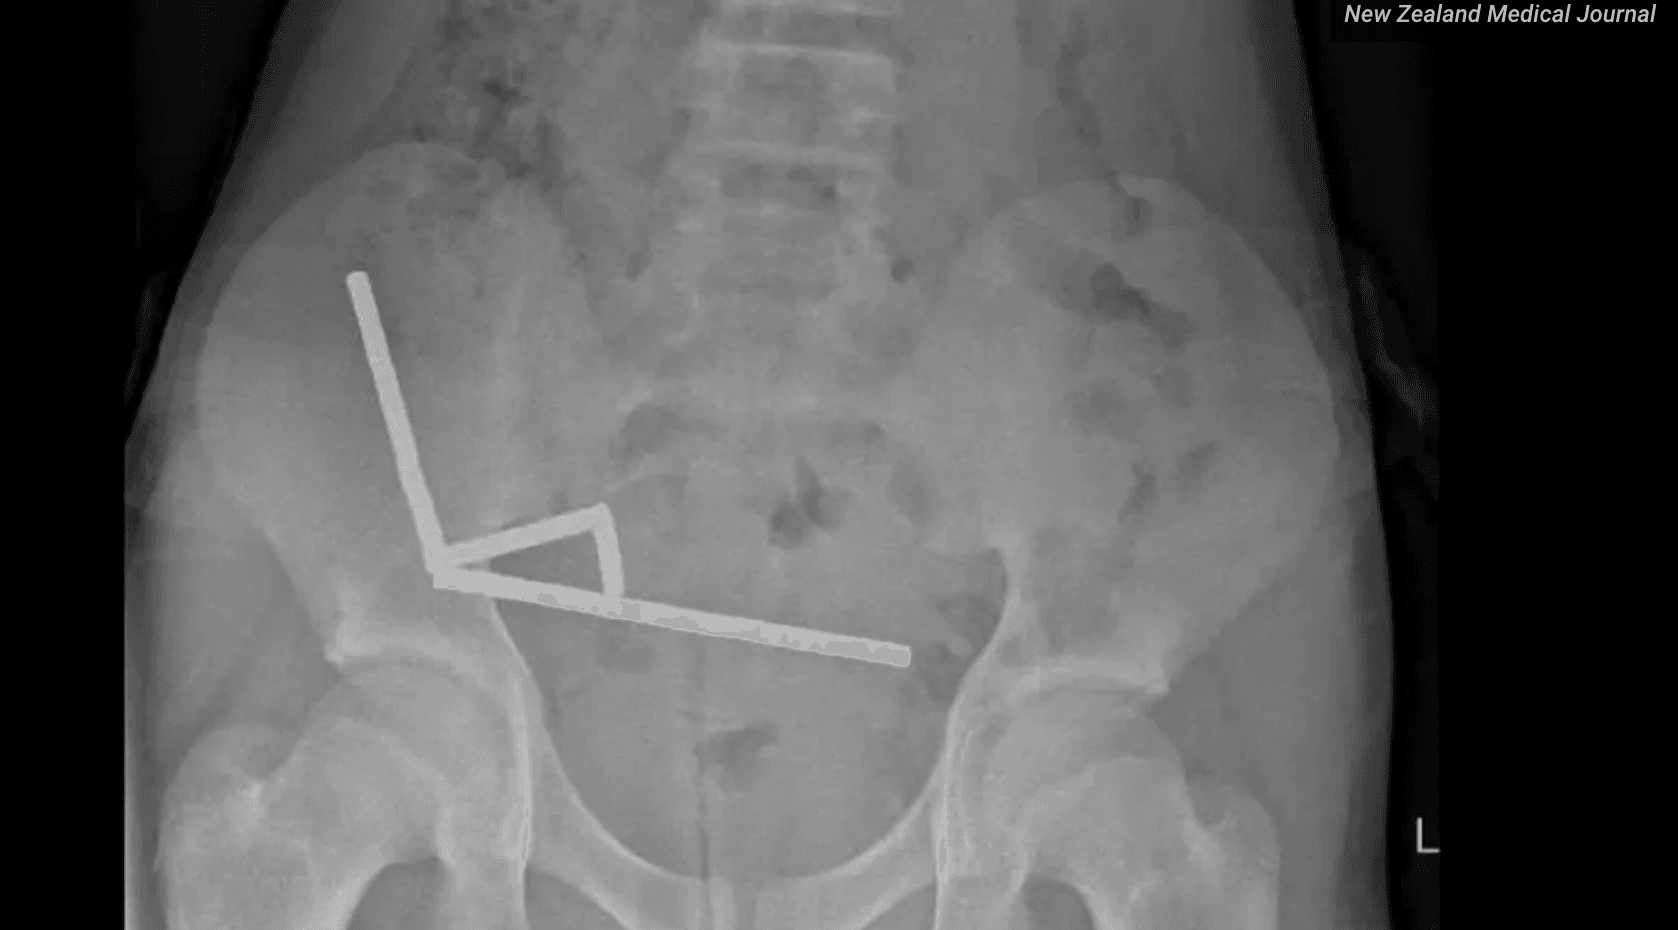

Lo que revelaron las radiografías y la operación de urgencia

Las radiografías mostraron una imagen muy clara y muy preocupante. En el interior del intestino aparecían varias líneas de pequeñas bolitas metálicas, agrupadas y pegadas entre sí. No estaban todas en el mismo tramo, pero la fuerza magnética las hacía atraerse, aunque hubiera paredes de intestino en medio.

Esa atracción tan fuerte hizo que diferentes partes del intestino se pegaran y se comprimieran. El tejido quedó atrapado entre los imanes y perdió riego sanguíneo. Los cirujanos describieron zonas con necrosis tanto en el intestino delgado como en el ciego, que es la primera parte del intestino grueso.